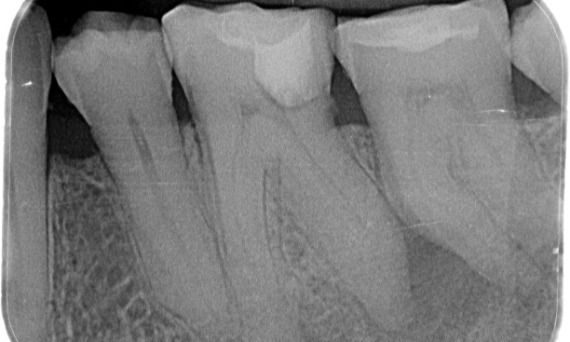

Before: Upon examination, there was a caries lesion related to the lower right first molar. Radiographic examination revealed proximity of the lesion to the pulp horn and combining it with the chief complaint, a final diagnosis of chronic irreversible pulpitis was concluded.

After: Access cavity was done as conservative as possible. TruNatomy was the system of choice due to the young patient’s age. We needed to preserve dentine as much as possible to increase the tooth ability to overcome occlusal load and increase the longevity of the final restoration.